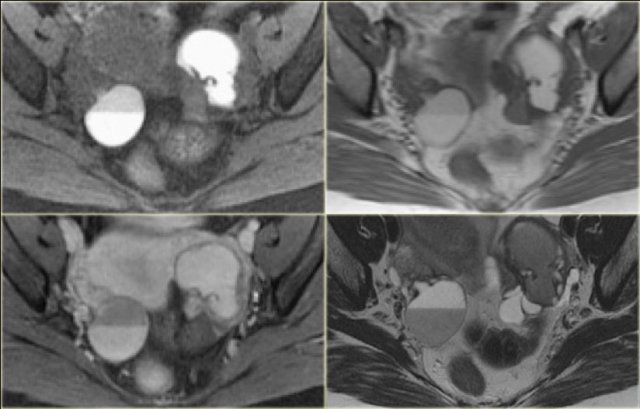

Hemorrhagic ovarian cyst in both right and left ovary Hemorrhagic ovarian cyst in both right and left ovary

The ultrasound images show the right and left ovary: on both sides there is what appears to be a solid lesion.

There is however good through transmission, which indicates that we are probably dealing with hemorrhagic cysts.

On Doppler US (not shown) there was no vascularity.

Continue with the MR examination.

Hemorrhagic ovarian cyst Hemorrhagic ovarian cyst

On an axial T1-weighted image both lesions are bright indicating fat, blood or high protein fluid.

Fat saturation does not suppress the signal in these lesions.

In an image with overall reasonably good fat suppression this rules out a fat-containing teratoma and confirms the suggestion of hemorrhagic fluid.

On the axial T2-weighted image both lesions show typical 'shading'.

The gradual drop in T2 is thought to be caused by a combination of increasing viscosity and increasing concentration of protein and iron towards the dependent portion of the lesion.

There is no enhancement on the subtraction image (Post-Gd minus Pre-Gd).

Again, subtraction is useful in cases like this: Gd-induced signal increase over the already very bright pre-contrast image would be very hard to appreciate otherwise.